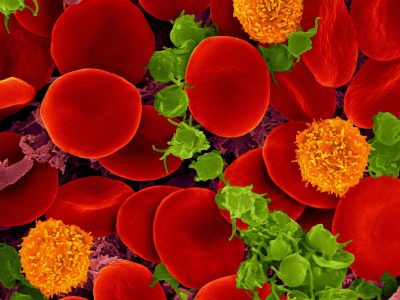

Un fenómeno catastrófico en una célula provoca la remisión del síndrome de WHIM en una paciente

- 17/02/2015